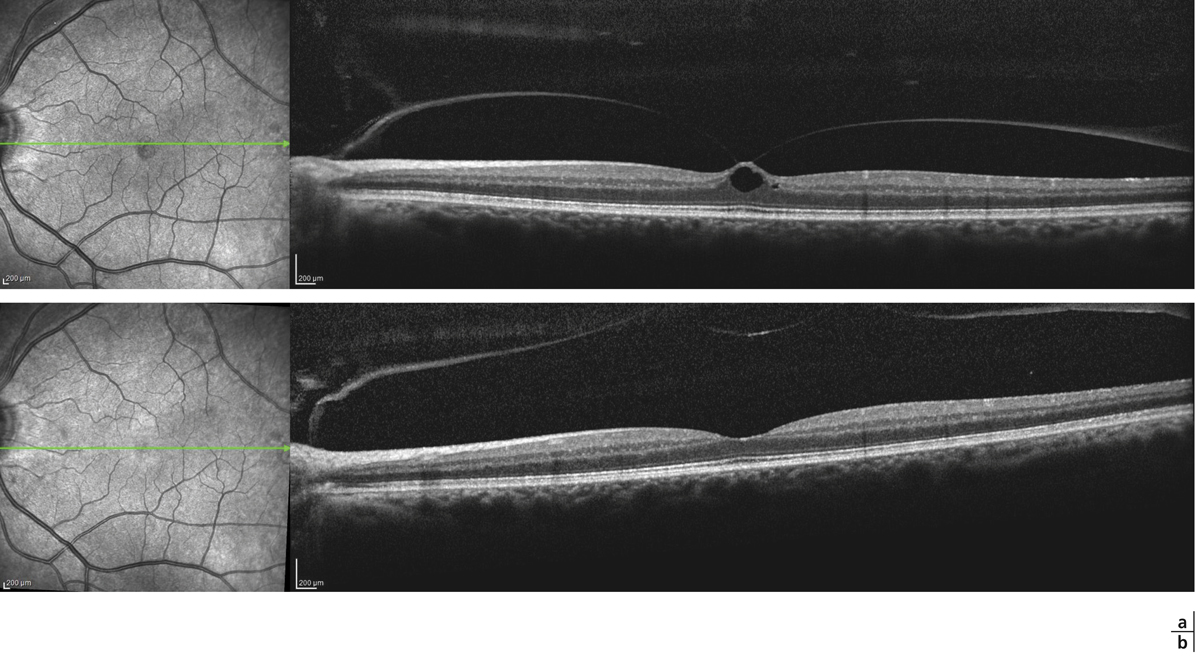

Fig. 13-5 Adhérence vitréomaculaire.

Fig. 13-6 Traction vitréomaculaire (TVM) focale.

a. La rétine externe est intacte. b. La TVM est plus marquée, la rétine externe reste intacte.

Fig. 13-7 Traction vitréomaculaire focale évoluée.

a. Traction vitréomaculaire focale évoluée, retentissement sur la rétine interne et externe. b. Aspect en 3D, l’adhérence hyaloïdienne reste focalisée sur la macula qui est soulevée. c. Résultat après la chirurgie associant vitrectomie et pelage.

Lorsqu’on analyse cette nouvelle classification, on note qu’elle décrit une évolution chronologique d’un DPV qui se déroule de façon anormale. Tout d’abord, sont décrites les AVM (fig. 13-5). Il s’agit d’un premier stade du DPV, DPV incomplet, où l’on constate que le vitré est décollé de chaque côté de la macula avec cependant la persistance d’une adhérence fovéolaire. Il n’existe à ce stade aucune force mécanique de traction sur la macula et il n’y a donc aucune modification anatomique de la fovéa en OCT. On ne peut pas encore parler d’évolution pathologique du DPV. En effet, il s’agit en général d’une découverte systématique faisant souvent suite à une atteinte maculaire de l’autre œil. Il n’y a aucune modification de l’acuité visuelle ni métamorphopsie.

Si le vitré reste adhérent à la fovéa, on constate la poursuite du DPV et on peut alors observer le stade de TVM. L’OCT montre dans ce cas une hyaloïde postérieure très réflective tirant sur la fovéa et induisant un épaississement maculaire. Le retentissement maculaire est très variable et dépend de la durée d’évolution (fig. 13-6). L’épaississement de la macula est variable. S’il est important, il peut alors exister une désorganisation d’un tissu rétinien externe avec de nombreuses logettes d’œdèmes cystoïdes (fig. 13-7a et b).

Avec la nouvelle classification, un nouveau paramètre est à prendre en compte et à mesurer, c’est la largeur du contact entre le vitré et la surface rétinienne. Ici, on parle de TVM focale ou étendue si cette zone de contact est inférieure ou supérieure à 1 500 µ (fig. 13-7c). Elle peut être isolée ou associée à une membrane épirétinienne.